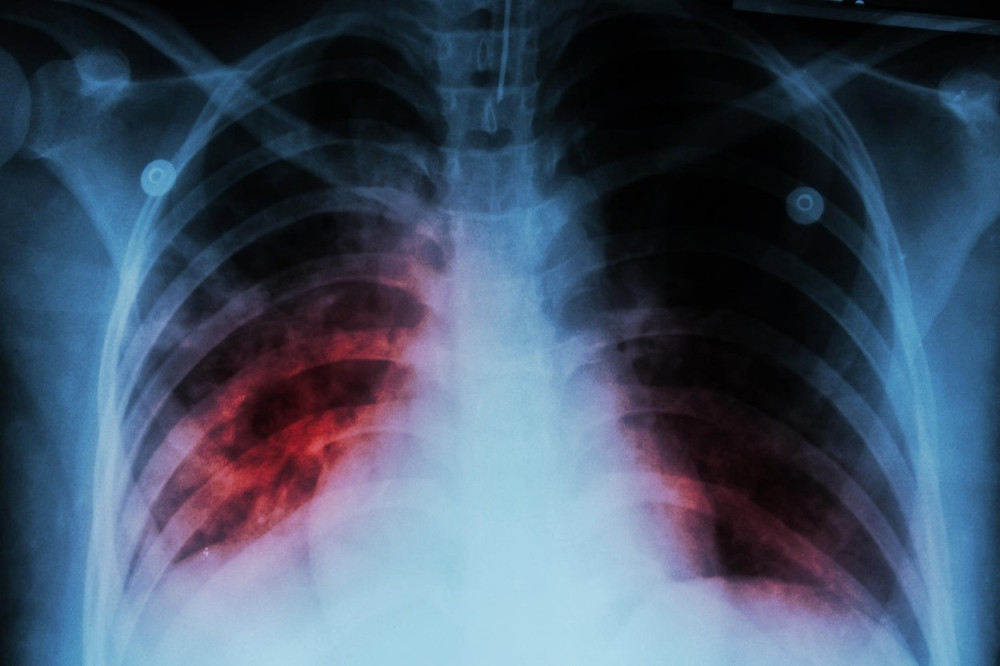

Tema: tuberkuloza